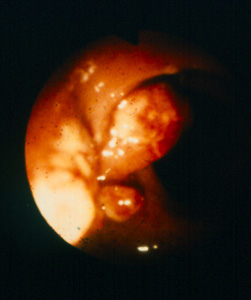

Slide Museum: Colon Cancer & Polyps : Colonoscopy showing inflammatory pseudopolyps of ulcerative colitis